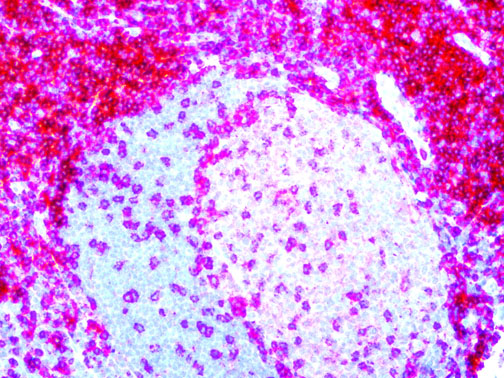

The first cytokines released are interleukin 1β (IL-1β) and tumor necrosis factor-α (TNF-α), which attract a variety of circulating white blood cells (WBCs) to the infection site, including neutrophils, monocytes, macrophages, and natural killer (NK) cells. This response, along with the antipathogenic chemicals released by these cells (i.e., complement), comprise the innate immune response. These cells directly attack the invading pathogen and also release additional cytokines, chief among them interleukin-1 and 6 (IL-6). IL-6 is essential for invoking the adaptive immune response, which calls T-cells, B-cells, and T helper (Th) cells to the infection site. IL-6 also stimulates further recruitment, proliferation and activation of macrophages.

It is the ICU physician who is most likely to witness one of the deadliest manifestations of the abnormal immunological response, the cytokine storm syndrome (CSS). This response is also referred to by some as the cytokine release syndrome (CRS). CSS is characterized by continuous activation and expansion of macrophage and lymphocyte populations, which secrete large amounts of cytokines, causing the cytokine storm. This massive cytokine release is akin to hemophagocytic lymphohistiocytosis (HLH) disease, a syndrome characterized by initial unchecked and persistent activation of cytotoxic T lymphocytes and NK cells.

Clinical and laboratory manifestations of HLH include fever, enlarged liver and/or spleen, neurologic dysfunction, coagulopathy, liver dysfunction, cytopenias (i.e., low levels of erythrocytes, leukocytes, and/or platelets), hypertriglyceridemia, hyperferritinemia, hemophagocytosis, and eventually diminished NK cell activity as the immune system becomes progressively paralyzed. HLH can be familial (primary HLH) or secondary to another disease process (sHLH), such as rheumatic disease, in which it is referred to as macrophage activation syndrome (MAS, characterized by elevated ferritin).